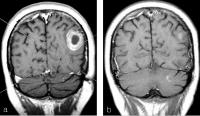

Akustikusneurinom - Planungs-MRT für Gamma Knife

Abbildung 3a-b: 3a: Zystisches Akustikusneurinom re, Gamma Knife Planungs-MRT (T1 mit KM, 3 mm). 3b: Kontroll-MRT nach 48 Monaten, signifikante Tumorregression